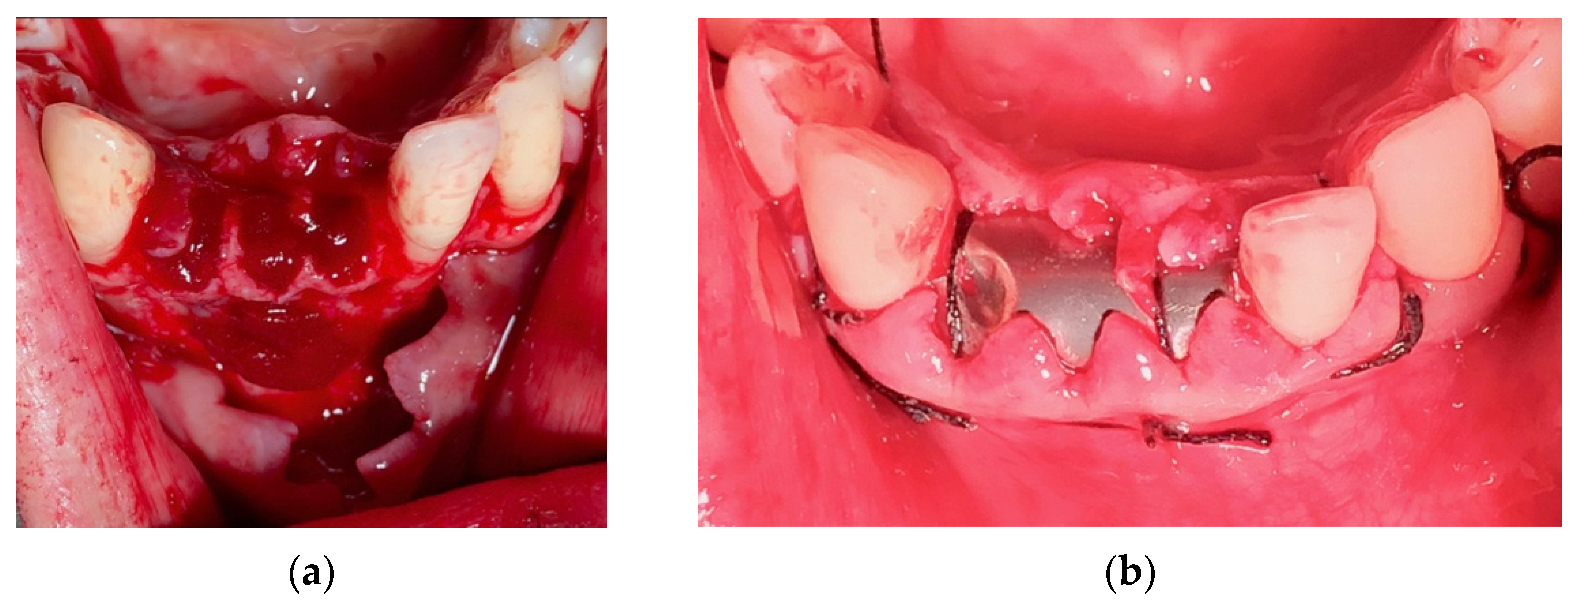

4.1. Clinical Case n.1.

4.2. Clinical Case n.2.

4.3. Clinical Case n.3.